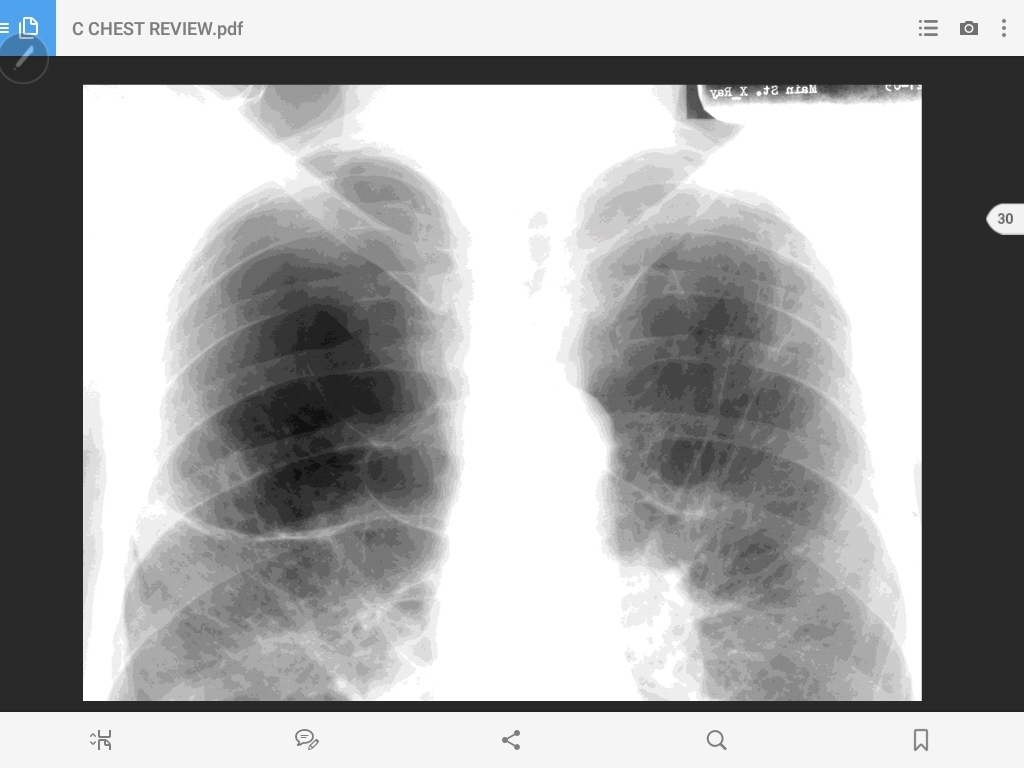

bullous emphysema

emphysema